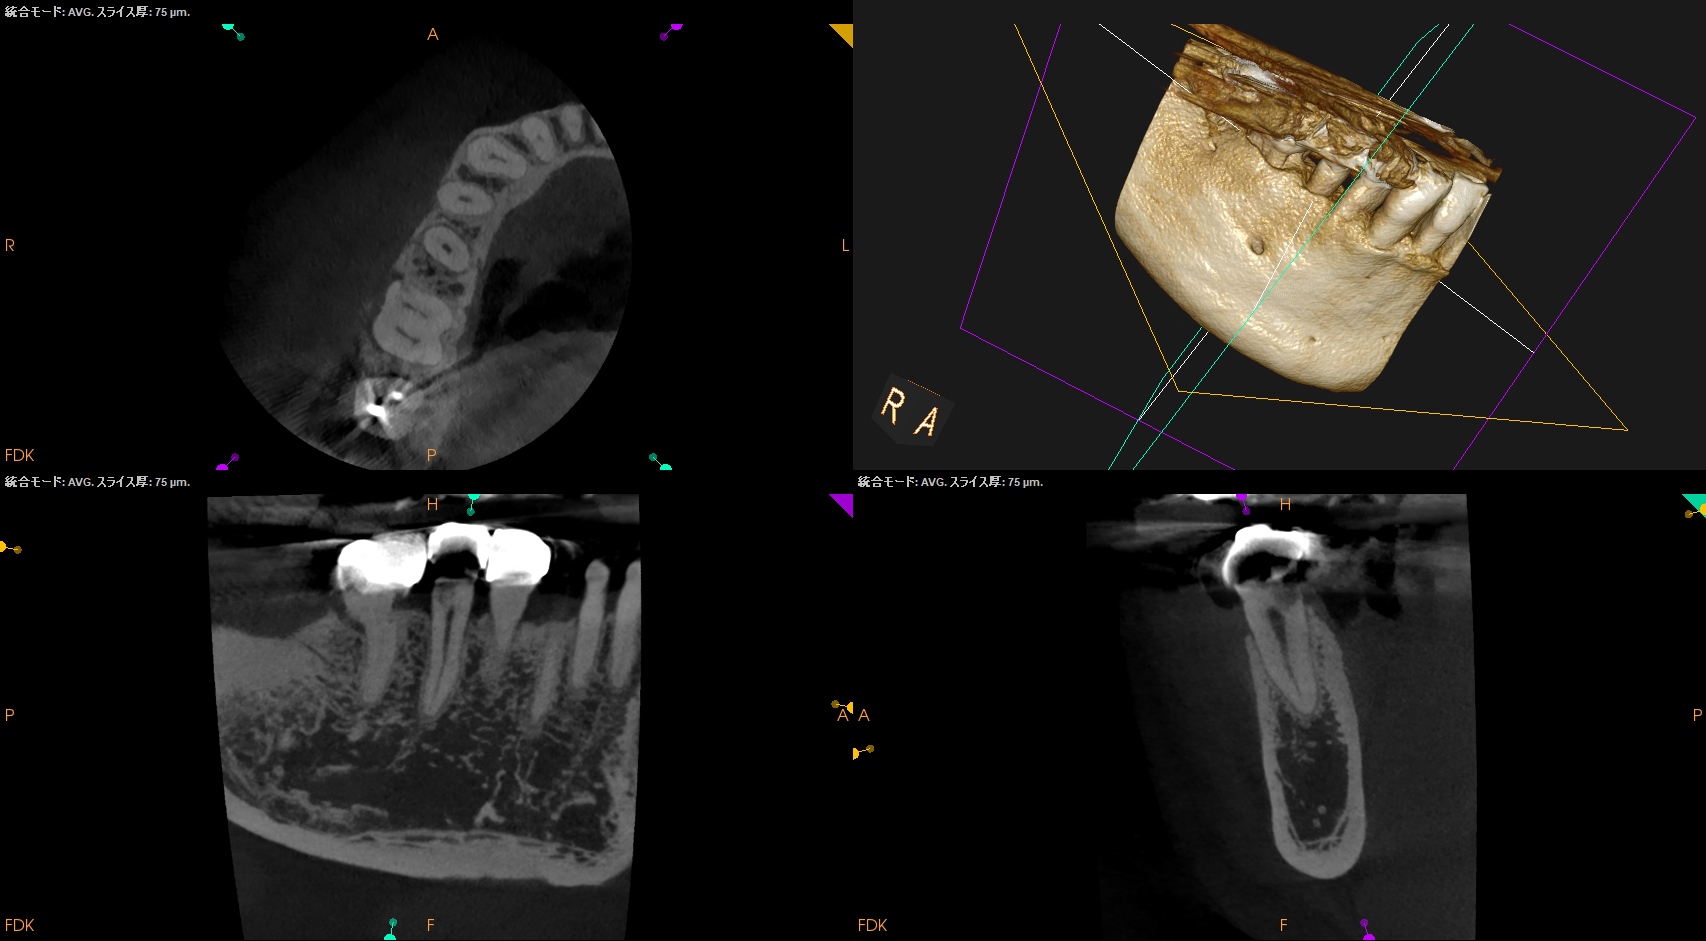

CBCT(2025.6.25)

が、根尖病変はない。

ここから臨床家が取れる行動は2つだ。

1つは抜髄して歯髄を除去する。

その際の成功率は96%(Sjorgren 1990)である。

もう一つは歯髄を保存する。

術前の検査ではCold testに対してWithin Normal Limit=WNLなので, その正当性はある。

が、その際の成功率は不明であるし、特典?としては歯髄が石灰化する。

その歯に感染が起きれば、歯髄は石灰化し根管治療はできずApicoectomy一択だろう。